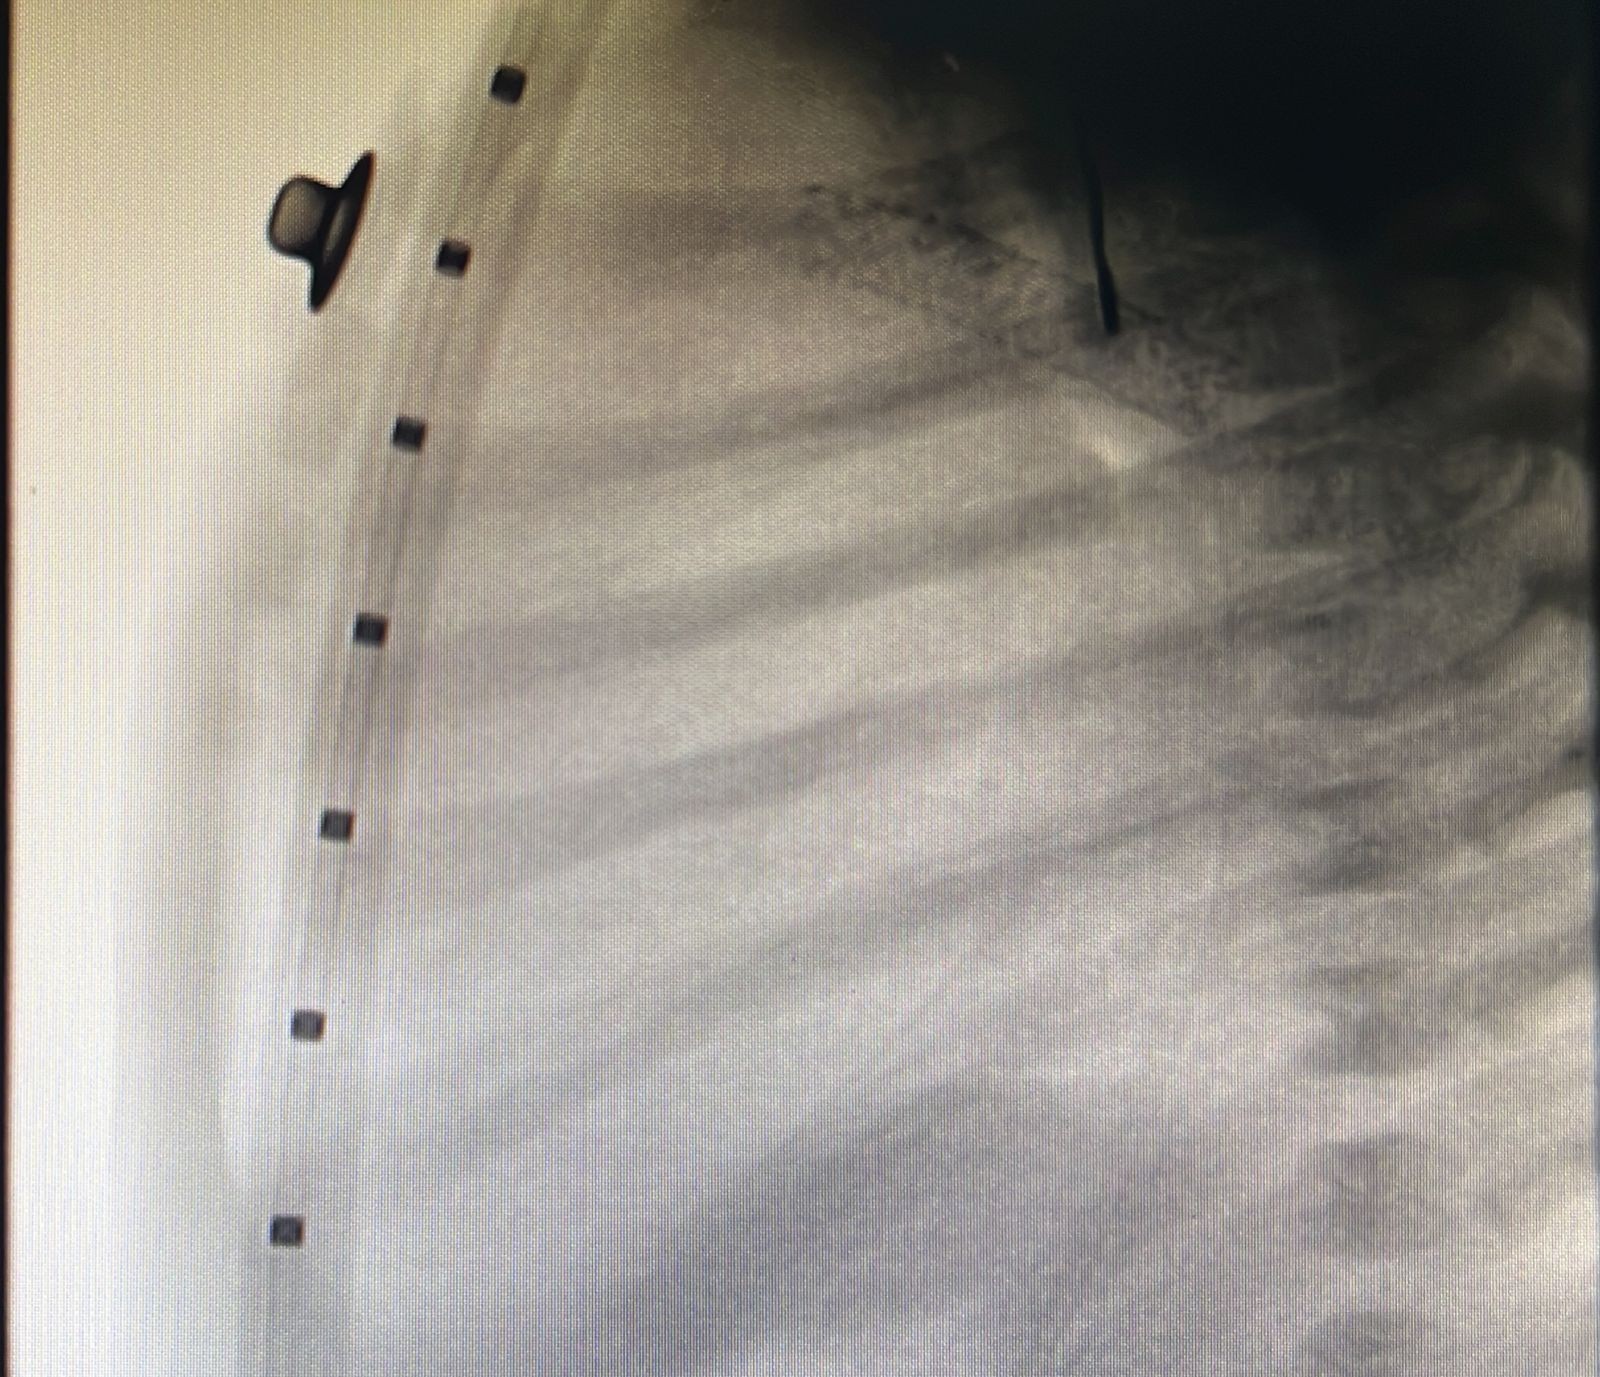

أنقذ تدخل طبي غير جراحي عاجل أجراه أطباء قسم أمراض القلب لدى الأطفال في مركز الأمير سلطان لطب وجراحة القلب بالقصيم، وعمل قسطرة قلبية لإنقاذ حياة رضيع حديث الولادة يبلغ من العمر ثلاثة أيام.

وأوضح تجمع القصيم الصحي أن الفحوصات والأشعة التي أجريت للرضيع الذي تم تحويله للمركز من خارج منطقة القصيم ويزن ثلاثة كيلوجرامات، أظهرت بوضوح أنه كان يعاني من انسداد كامل في صمام الشريان الرئوي؛ مما تسبب له بانقطاع تام للدورة الدموية لكامل الجسم.

وأشار التجمع إلى أنه تم خلال التدخل الطبي غير الجراحي تركيب دعامة للقناة الشريانية ما بين الشريان الأورطي والرئوي بهدف إيصال الدم للرئتين، إضافة إلى توسيع ثقب أذيني لاستفادة الجسم بخلط الدم المؤكسج وغير المؤكسج، وقد تكللت عملية القسطرة بالنجاح، وبعد الاطمئنان على وضعه الصحي غادر المركز برفقة ذويه وهو في حالة مستقرة ولله الحمد.